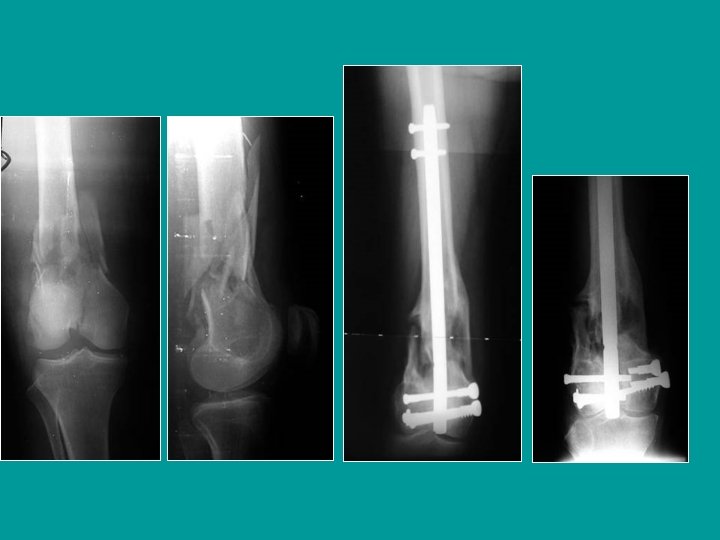

12 años: traumatismo en hiperextensión de la rodilla Salter-Harris tipo I, muy desplazada

Reducción de los desplazamientos en hiperextensión Tracción en el eje de la pierna, con la rodilla en flexión, mientras que reposicionamos la epífisis presionando hacia atrás y distal +/- corrección lateral

Enclavijado percutáneo

Resultado después de 5 semanas (clavijas retiradas previamente)

Salter-Harris tipo I, muy desplazada: reducción y enclavijado percutáneo

7 años Fémur: Salter-Harris I Tibia: Salter-Harris II Parálisis del Ciático Poplíteo Externo Pulsos normales Después de 3 meses: recuperación progresiva

Niño de 7 años Accidente con vehículo agrícola Fracturas cerradas Pulsos presentes Parálisis del nervio Ciático Poplíteo Externo Fractura de Salter-Harris tipo 2 en fémur y tibia Reducción de las fracturas Luego de 3 meses: Algunos signos de recuperacion: No existe indicación para realizar una Electromiografía Fotos: F. CHOTEL